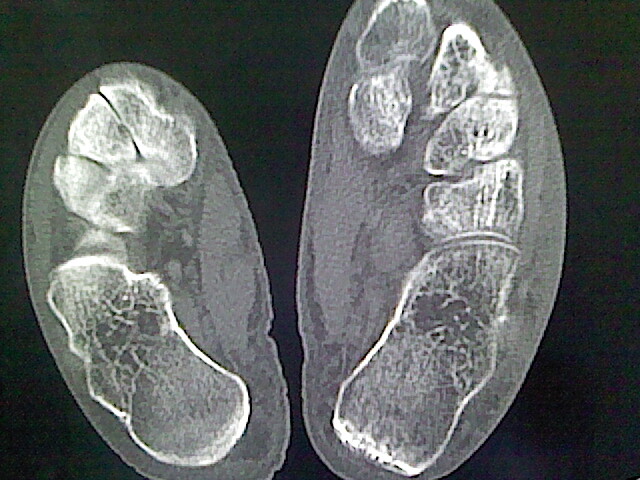

明显骨质疏松,建议本周是蛋白测定

警惕滑膜肉瘤可能

骨病经验少看不好,退行性骨关节病的改变是有,但软组织广泛肿胀又不是骨感染来的、又不是肿瘤破坏来的、又不是代谢病来的、又不是外伤所致......有脉管病吗?